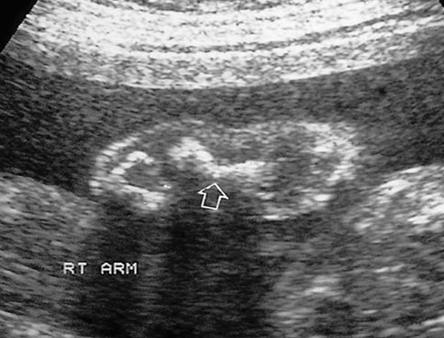

Amelia